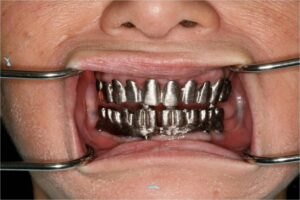

- Προσθετικη επι εμφυτευματων